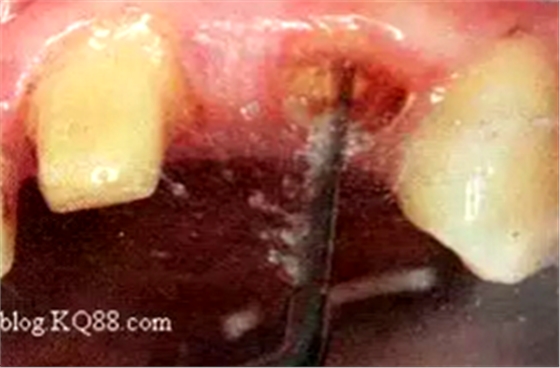

2. 清除根管壁殘留物

根管壁殘留物的存在直接影響纖維樁的粘接和固位,這也是導(dǎo)致纖維樁脫落的主要原因。

(根管內(nèi)殘留物)

個(gè)人見解:必要的情況下先開闊根管口建立一定的視角后,慢速手機(jī)上G鉆為引導(dǎo)鉆,由號(hào)遞增引導(dǎo)開闊通路;P鉆預(yù)備樁道,同樣需要由小向大號(hào)遞增,直到選擇好適合的號(hào)預(yù)備到規(guī)定測(cè)量的深度即可,再配合纖維樁系統(tǒng)中各型號(hào)纖維樁所匹配的樁道鉆,預(yù)備、修整成與纖維樁相適應(yīng)的樁道。

預(yù)備后根管壁上會(huì)不同程度的牙膠和封閉劑等殘留物,所以樁道預(yù)備前后建議X線片輔助檢查預(yù)備深度等情況,而殘留物也會(huì)很清晰地顯現(xiàn)。

根管銼去除殘留物,很難去除干凈,而備取樁道時(shí),禁止使用牙膠溶解劑(如:丁克除、氯仿)等有機(jī)溶劑去除殘留物,以防破壞根尖區(qū)牙膠的封閉和防止附著根管壁影響粘接。

(超聲去除根管殘留物)

通常此時(shí)以超聲潔牙機(jī)更換較細(xì)工作尖進(jìn)入根管(根管消毒沖洗液配合清潔工作后面會(huì)提到),徹底去除樁道根管壁上的附著殘留物,效果明顯。再配合X線片、根管顯微鏡輔助檢查清理的情況下更佳。